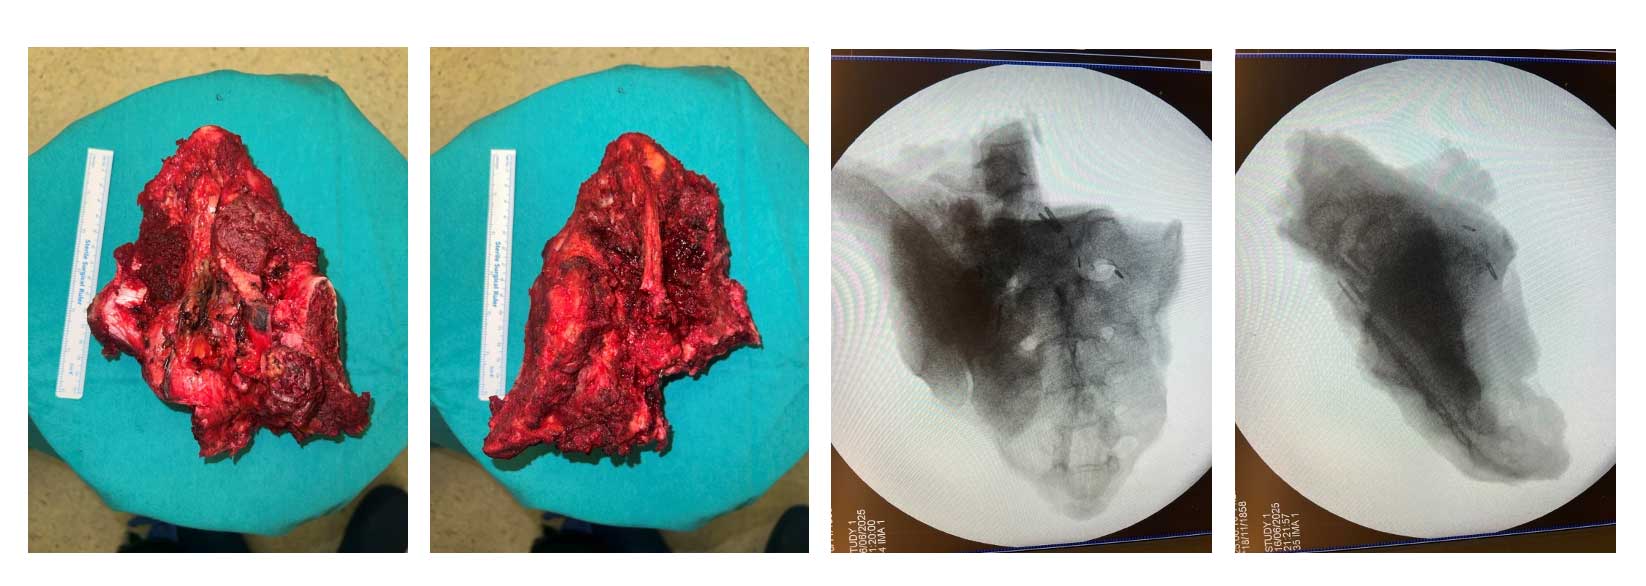

Ameliyat Esnası: Rezeksiyon dokusunun klinik ve skopi görüntüsü.